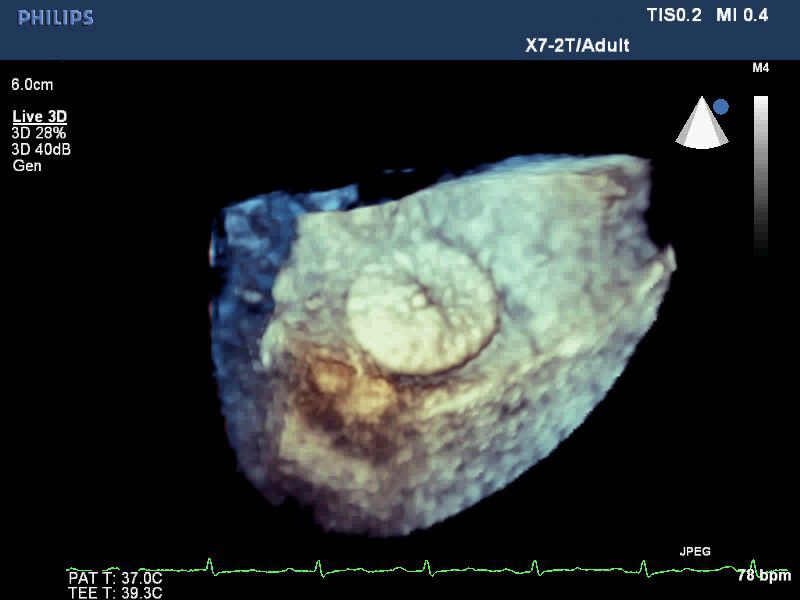

• 3D-эхокардиография в реальном времени с углубленным количественным анализом

• Улучшенная визуализация с помощью матричных датчиков при проведении 3D-эхокардиографии

• Live 3D TEE: Эта функция позволяет проводить чреспищеводную эхокардиографию в режиме реального времени, что позволяет оценить механические сокращения сердца с точностью, необходимой для оценки результатов хирургического вмешательства.

• Live 3D Echo: Эта функция позволяет получать объемные 3D-изображения анатомии и механики сердца в режиме реального времени, расширяя возможности эхокардиографии.

• 3D эхо-кг в реальном времени (Live3DEcho): Эта технология позволяет получать объемные 3D изображения сердца в режиме реального времени.